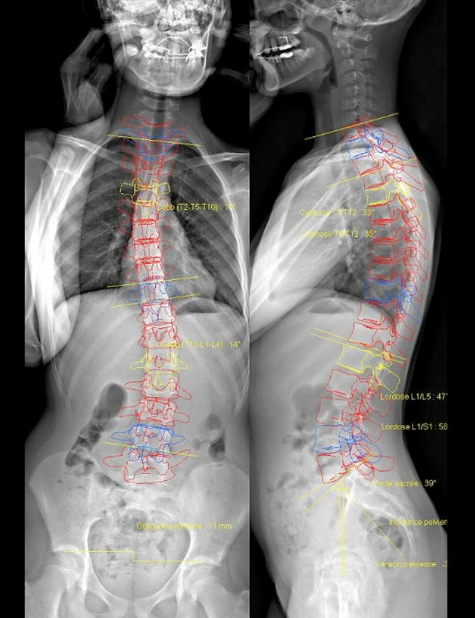

L'une des caractéristiques les plus remarquables de la cabine EOS est sa capacité à produire des images tridimensionnelles du squelette de haute qualité, en position debout. Cette visualisation avancée permet aux médecins d'analyser avec précision les structures osseuses et les articulations et leurs différents angles, offrant ainsi une compréhension plus complète des morphologies osseuses et des anomalies anatomiques.

La cabine EOS se distingue par sa capacité à produire des images d'une netteté et d'une précision exceptionnelles. Grâce à une technologie avancée de balayage, elle capture des images radiographiques haute résolution avec une exposition extrêmement faible aux rayons X, réduisant ainsi considérablement l'exposition aux radiations pour les patients et le personnel médical.